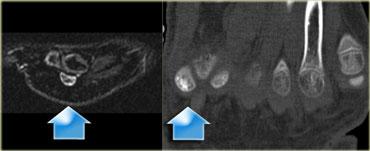

Hình bên trái: nam bệnh nhân 14 tuổi, cầu thủ bóng đá, với triệu chứng đau lòng bàn chân vùng mu dai dẳng.

Gãy xương do stress của xương vừng trong ngón cái được xác định bởi tăng tín hiệu

trên chuỗi xung STIR mặt phẳng đứng dọc

tại thời điểm khám.

CT thực hiện tại thời điểm khám cho thấy xơ cứng xương vừng trong và xác nhận chẩn đoán gãy xương do stress.